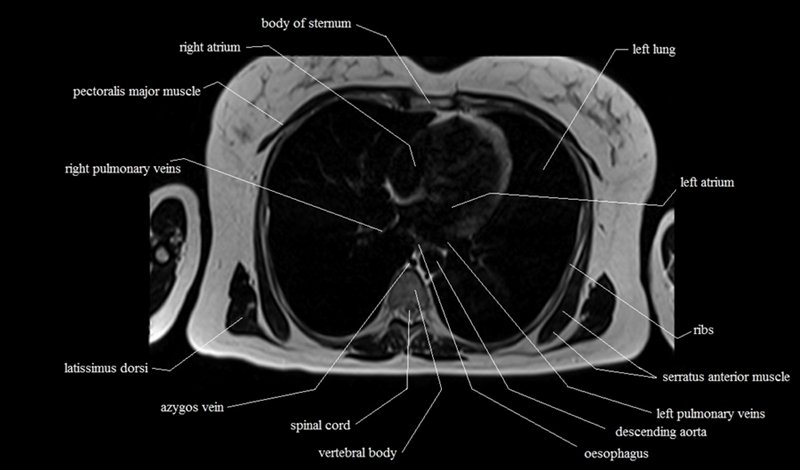

MRI Axial Cross Sectional Anatomy of Chest

This MRI chest (thorax) axial cross sectional anatomy tool is absolutely free to use. Use the mouse scroll wheel to move the images up and down, or alternatively, use the tiny arrows (→) on both sides of the image to navigate through the images. For a more detailed view, double-click the image to view it in full screen, and use the menu in the top right-hand corner to view individual slides or play them in a loop.